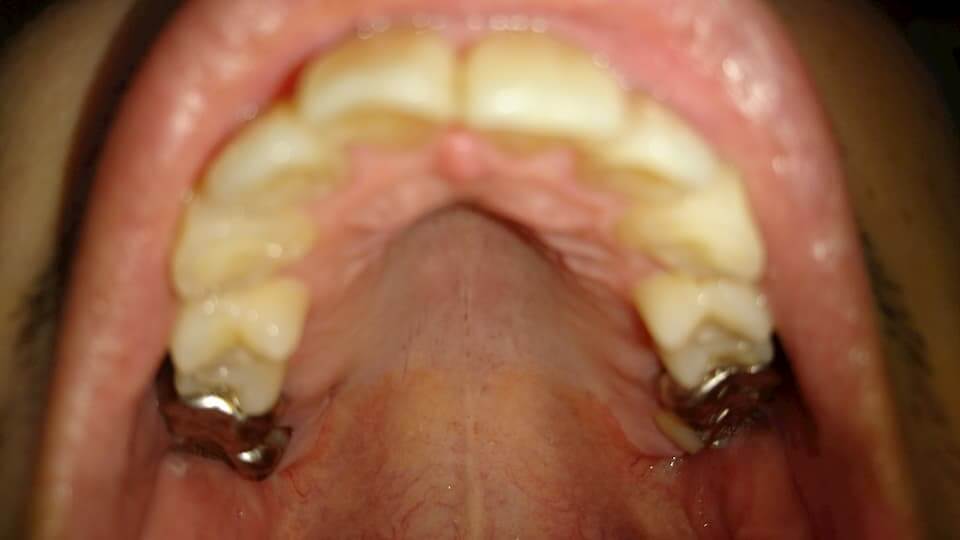

歯の写真

下の第1、2小臼歯辺りがマウスピースをはめていても痛かった。

外すと歯が戻ろうとするのか犬歯から大2大臼歯辺りまで痛みが出る。

まだ歯の位置が定着していないみたい。